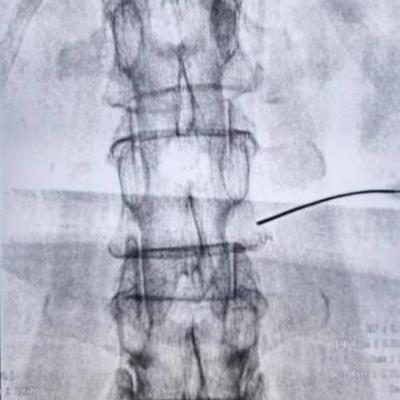

腰交感射频术是在超声引导下将0.7mm(绣花针那么细)的射频针达L2和L4椎体前外侧的交感神经节处,达到目标靶点后,再借助CT\X线做最后定位。

超声引导结合影像定位是疼痛科的特色技术。超声具有可视化、实时动态观察、准确率高、无辐射等优点,就像精确制导导弹一样,同时又可避免对靶目标周围血管、神经的损伤,从而达到理想的治疗效果。